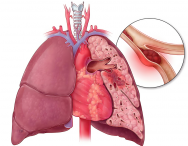

西安市长安区医院介入血管科成功救治高危型急性肺动脉栓塞

近日,西安市长安区医院介入血管外科团队与多科室通力协作,成功为一名急性高危型肺动脉血栓栓塞症患者实施了急诊肺动脉机械血栓清除术,将患者从死亡边缘奋力夺回。此次抢救...